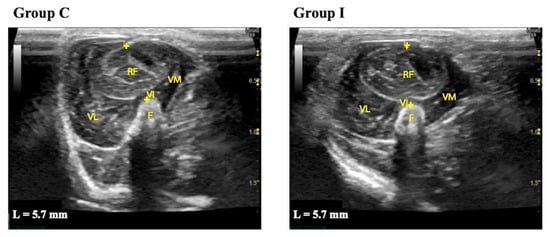

3.2. Measurement of Thigh Muscle Thickness

Representative measurements of thigh muscle thickness are shown in Figure 1. The hypoechogenicity of muscle fibers and hyperechogenicity of perimysium and fascia were observed.

The measurements of quadriceps muscle thicknesses are shown in Table 3. The quadriceps muscle thickness in Group I was decreased in all periods compared to Group C. In Group C, on the other hand, the quadriceps muscle thickness increased as the rats grew.

Figure 1. Representative transverse B-mode ultrasound images of the quadriceps muscle used to measure muscle thickness before the experiment. Group C, control group; Group I, immobilization group; L, thigh muscle thickness. F: femur; RF: rectus femoris; VL: vastus lateralis; VM: vastus medialis; VI: vastus intermedius; +: electronic caliper. The images show the placement of the electronic calipers to measure the cross-section at 50% of the femur length by passing across the center of the rectus femoris muscle from the surface of the muscle to the femoral bone.